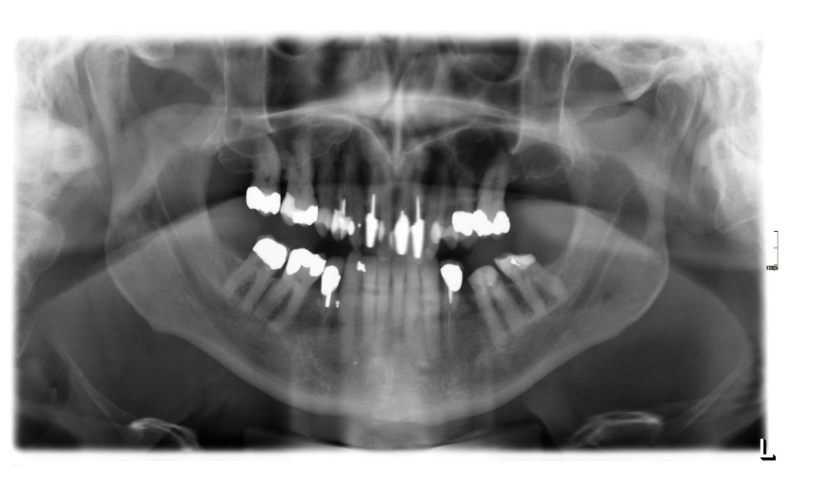

Skarpa skiktet

Det gröna fältet i mittenbilden ovan är det avbildas skarpt av maskinen. Om patienten inte är korrekt placerad i maskinen avbildas inte patienten inte optimalt.